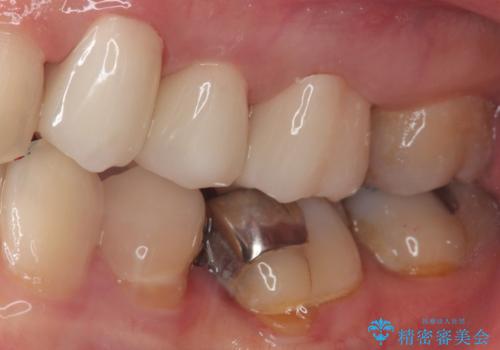

銀歯を外すとかなり大きな虫歯になっていました。幸いぎりぎりのところで神経まで虫歯は広がっていなかったため、症状が出ない事を確認した後、オールセラミッククラウンで治療しました。虫歯除去後、残っている歯質が少なかったため、破折抵抗を考慮し部分的な被せ物ではなくクラウンを選択しました。

※被せ物では歯と被せ物の適合がとても大切になります。適合が悪い被せもの(歯と被せものの間に隙間がある)を入れるとそこに汚れが溜り虫歯の原因となります。当院では精度が高い被せものを追求するため、サージテル(拡大鏡)や型取りの材料にシリコン材を使用しています。